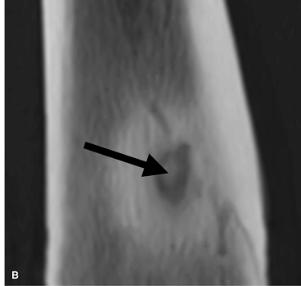

Чтобы диагностировать это заболевание необходимо сделать рентген. На снимке врач видит полость в губчатой части кости диаметром от 2 до 2,5 см, которая окружена по бокам зоной склероза. Внутри полость наполнена гноем, а также кровянистой или серозной жидкостью. Также при детальном осмотре в ней виден тканевый детрит.